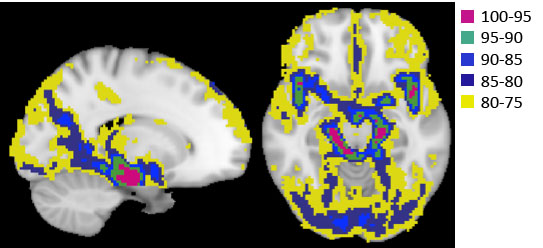

Fig.2. The quantified CBVa map (A) and pulsatility map (B).

Figure 1 shows ROIs determined by CBVa values (see Fig. 2A), representing different sized arteries, from large to small. Figure 2 demonstrates quantified CBVa and pulsatility maps agree strongly. The pulsatility and CBVa values from each ROI were found to be closely related with pulsatility = 0.63×CBVa (ml/100g) – 0.33 (Fig. 3). The ratio of pulsatility was exponentially decreased from large to small arteries, and the exponential decay constant varied in each individual (Fig. 4A). This was significantly decreased with mean BP and diastolic BP (Fig. 4B and 4C), but was not significantly related with systolic BP (p=0.37, R=0.24).